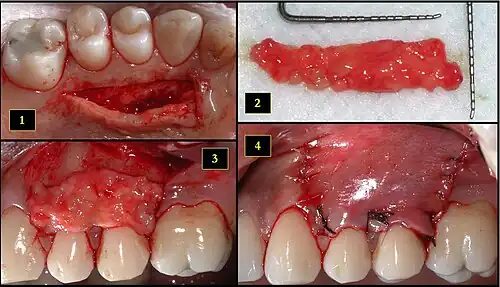

1. Recipient site exhibits gingival recession on both premolars and first molar (molar recession is not an esthetic issue and will not be treated)

2. Incisions prior to flap reflection

3. Full thickness flap elevated

4. Another viewpoint of the flapped recipient site